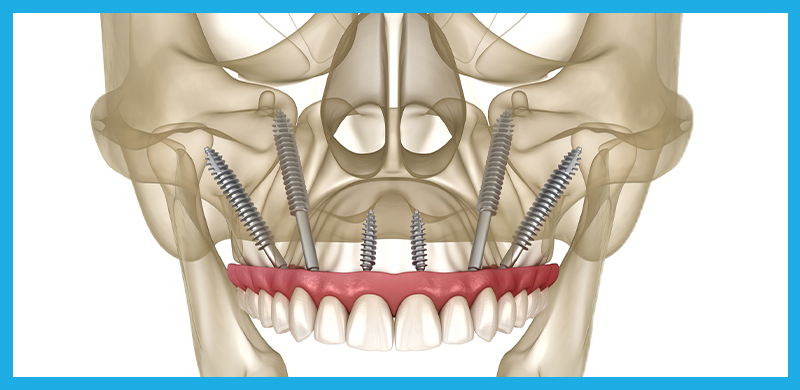

Zygomatic Implants, also known as no-bone implants, are the ultimate solution for patients who have been told they don’t have enough bone for traditional dental implants. This highly specialized procedure is designed for individuals with severe bone loss, and it requires an extraordinary level of skill and experience. At OneSolution® Dental Implant Centers, we are among the very few in the country with the expertise to perform this life-changing procedure.

- Zygomatic and Pterygoid Implants: A Faster Solution: Traditional dental implant methods often require extensive bone grafting and a lengthy healing period, sometimes taking up to a year before final teeth are placed. Zygomatic and Pterygoid Implants bypass the need for bone grafts by anchoring the implants in the cheekbone and pterygoid plate, allowing for immediate loading of teeth. This not only shortens the treatment time dramatically but also provides a solution for patients who were previously told they weren’t candidates for implants due to severe bone loss.

The Procedure: